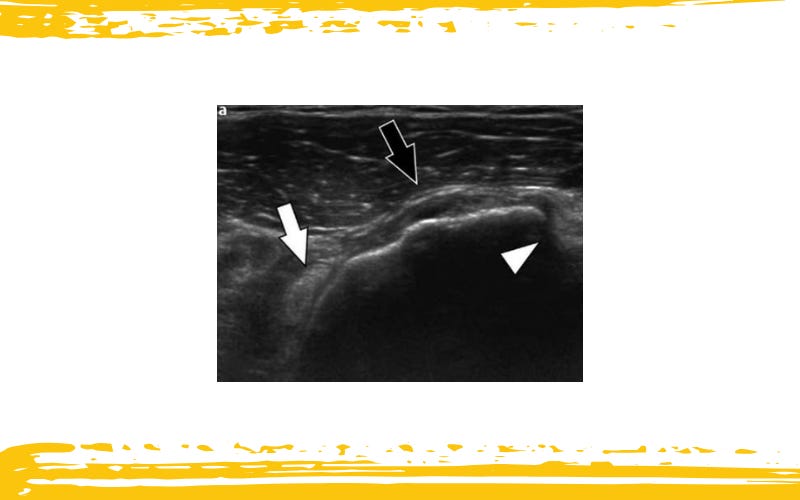

Imágenes ecográficas de:

(C) rotura del tendón del subescapular, y (D) rotura del tendón del infraespinoso.

La ilustración situada en la esquina inferior izquierda representa la posición del transductor. Las flechas señalan los sitios de la rotura.

Rotura completa del Tendón Subescapular (Flechas negras) asociada a una dislocación intraarticular de la cabeza larga del Bíceps (Flechas blanca).